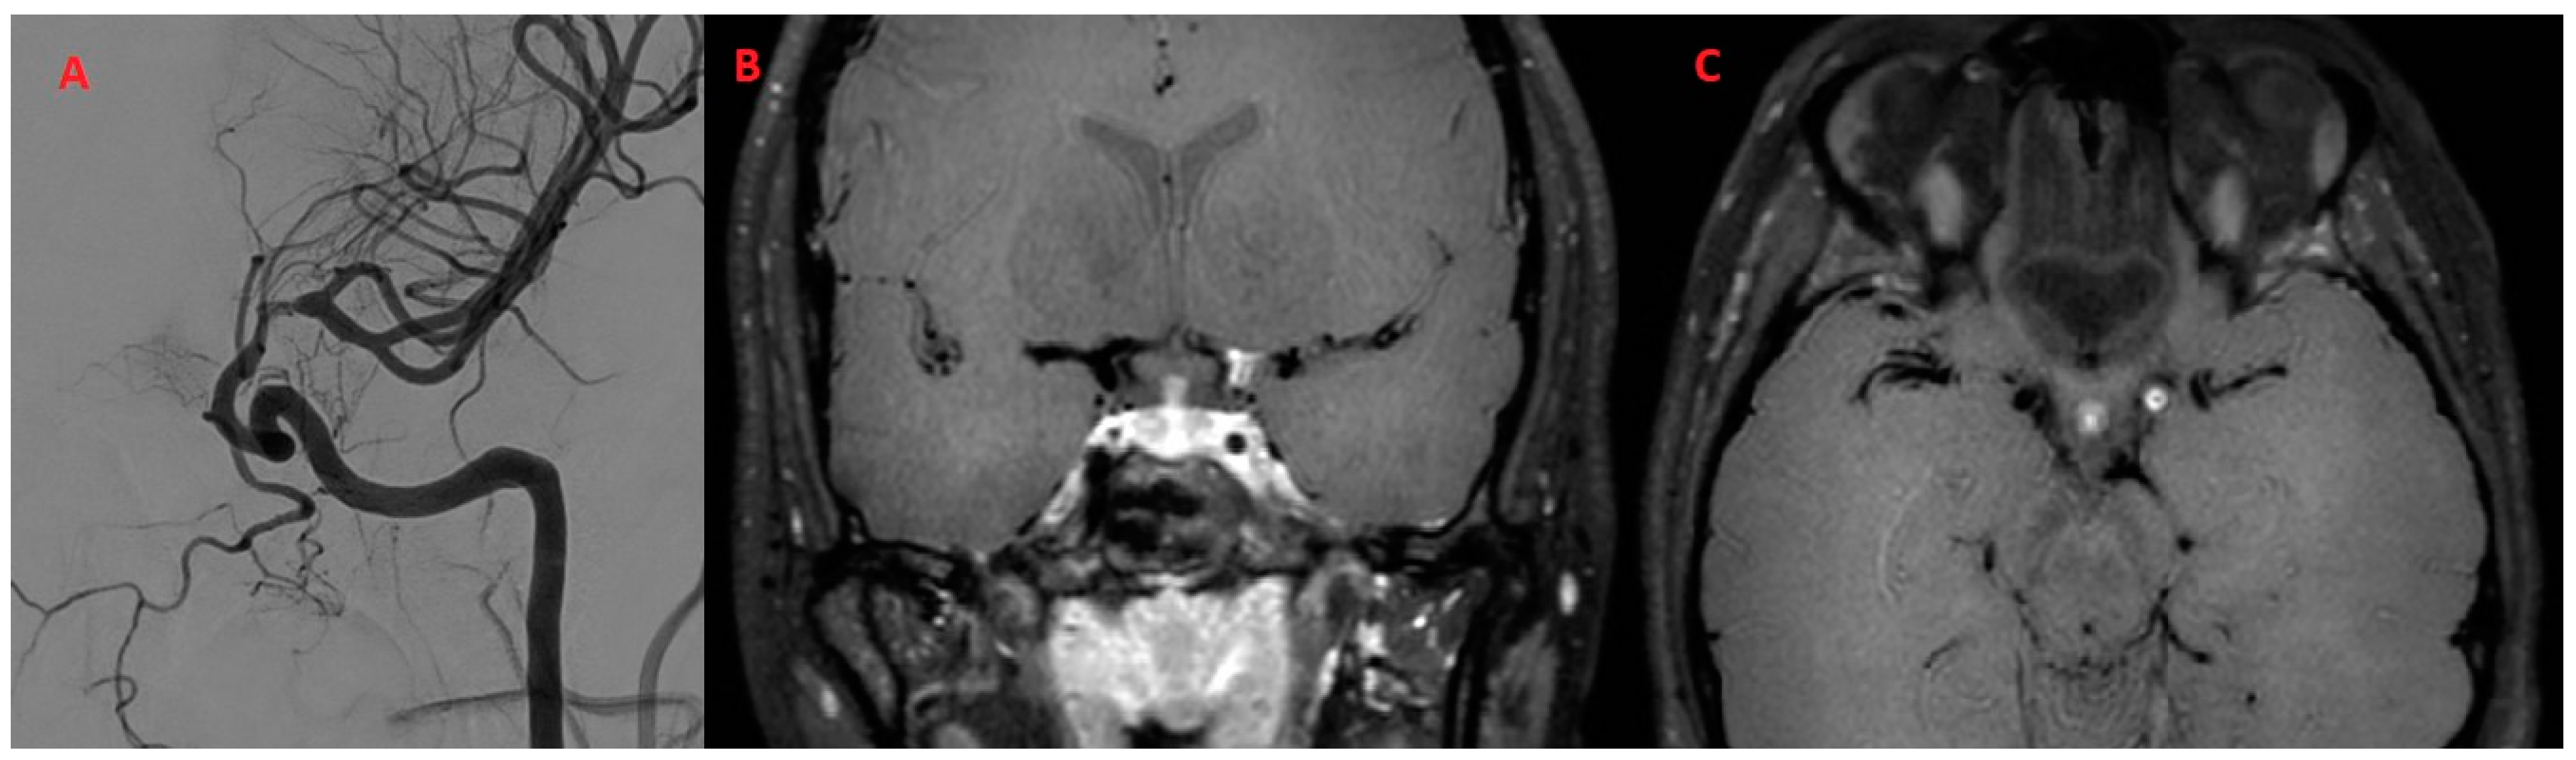

| 66Y, M | 3 | Present | Present | Bilateral Basal Ganglia, Left SCA | SCA | ACM (M1) ICA BA | Present | Subtentorial |

| SCNSV Systemic disease (n = 4) | 3 (75.0%) | 2 (50.0%) | 0 (0.0%) | 2 (50.0%) | 2 (50.0%) | 2 (50.0%) | 3 (75.0%) | 2 (50.0%) | 0 (0%) | 3 (75.0%) | 0 (0%) | BA, VA, SCA, ICA, ACM (M1), PCA (P2) |

| multiple: 3 (100.0%) | ||||||||||||